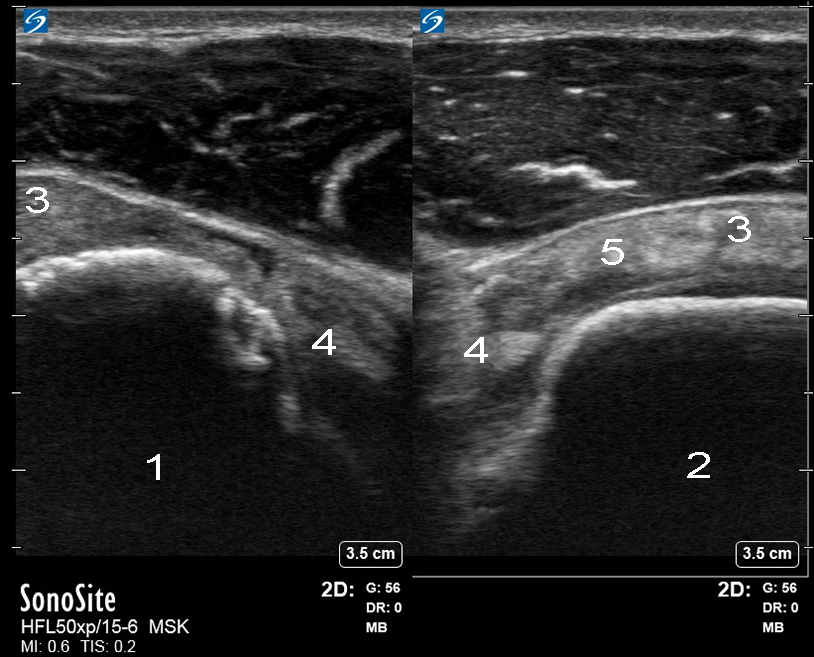

肩回旋腱板損傷画像

腱板疎

右

左

棘下筋

上腕二頭筋腱(BT)

棘上筋